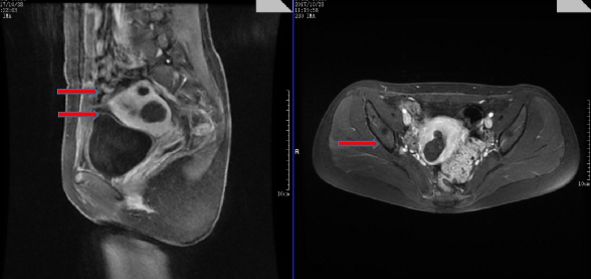

以下是劉女士術(shù)后的核磁影像(箭頭所指即為已經(jīng)缺血壞死的肌瘤)

劉女士術(shù)后第二天就出院且恢復(fù)非???,治療后的四個月就順利受孕,并在市婦幼院婦產(chǎn)科專家指導(dǎo)下進行規(guī)律產(chǎn)檢。孕期超聲提示胎兒生長一切正常,各項檢查結(jié)果也都正常。與此同時,超聲顯示已經(jīng)“死掉的”子宮肌瘤有的已經(jīng)消失不見。